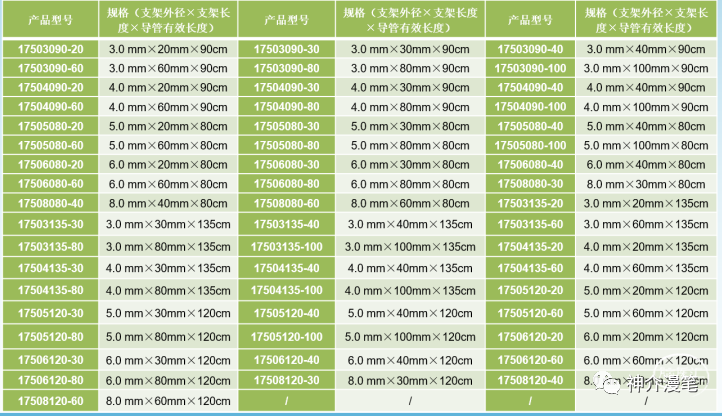

3-6的支架可以使用4F鞘或6Fguiding进行释放,下图为其常见支架型号。

最后来一个汇总图吧,把所有支架的参数放在一起,大家一块比一比,这样心中就都有数了。